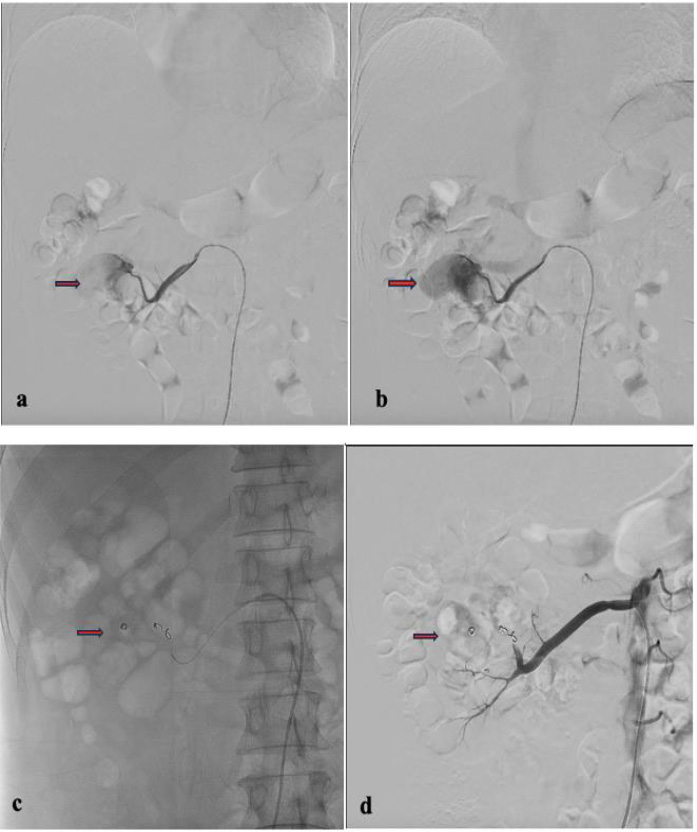

In the first procedure, we found a single pseudoaneurysm originating from the right renal middle pole segmental artery during the embolization procedure. We used VortX pushable coils (3.3 mm and 4.0 mm) and PVA 600 to do superselective embolization on the right renal middle pole segmental artery branch (Fig. 2). While the main artery, the right renal artery, remained patent, the right renal segmental artery underwent significant embolization. The immediate outcome was favorable, with a cessation of visible bleeding. The patient also received antibiotic therapy, analgesics, and injection hemostasis; underwent blood clot evacuation and received red cell transfusions.

Angiography with a Cobra catheter and microcatheter. (a, b) Pseudoaneurysm in the right renal middle pole segmental artery; (c) Superselective embolization; (d) Angiography after embolization showed the bleeding artery is successfully occluded.